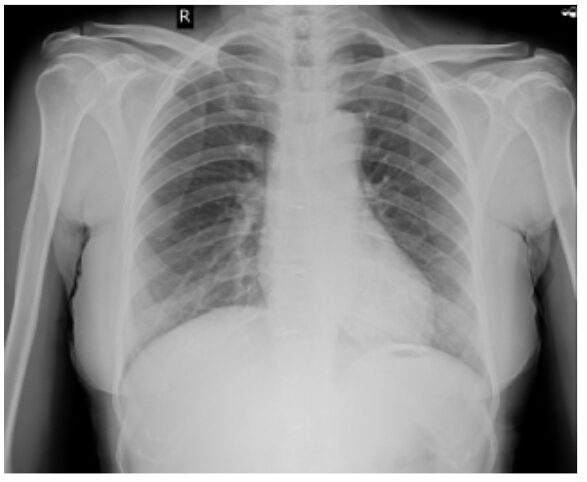

RS : BAE+, NVBS